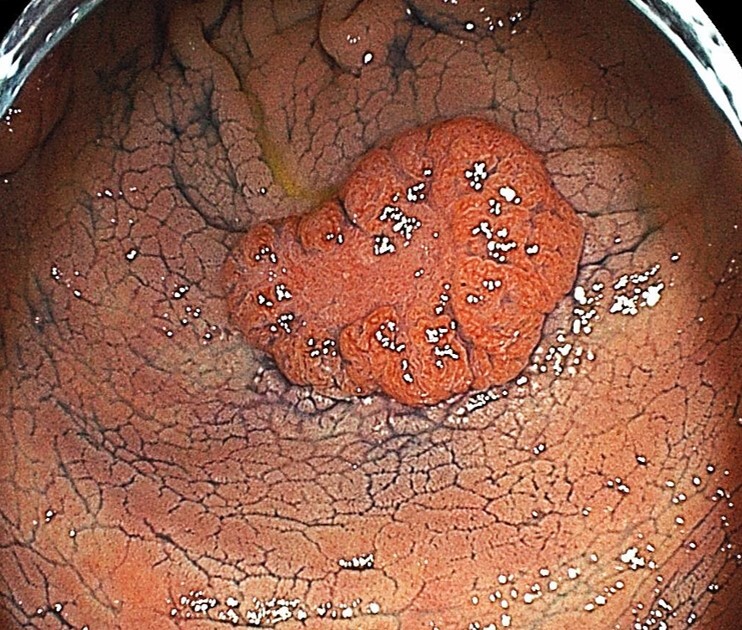

大腸ポリープというイボのような病変が見つかることがあります。

小さい病変の多くが腺腫と言われる良性の病変ですが、徐々にサイズが大きくなり1cm以上になりますと大腸がんとなる可能性が高くなります。

よって、サイズの小さい内に治療することが、大腸がんの予防にもつながります。

当院では出血や腹痛 (腹膜炎)などの合併症が少ない治療法 (コールドスネアポリペクトミー)により、検査同日の日帰り治療も行っています。

良性病変、当院で切除治療を行い根治

良性病変、他院で切除治療を行い根治